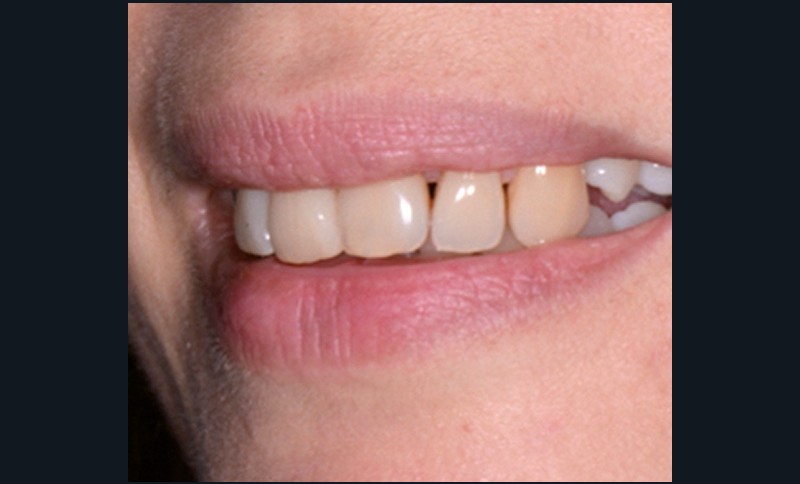

Sur les figures 1a et b, les trois étages de la face sont équilibrés. Le sourire met en évidence une légère bascule du plan d’occlusion.

Les muscles orbiculaires se contractent lorsque les lèvres sont jointives. Le sourire est spontané, large et les lèvres sont charnues. La courbe du sourire est satisfaisante de 12 à 22 puis les dents rentrent, disparaissent de face et apparaissent plus hautes sur le sourire de trois-quarts. Les incisives maxillaires sont bien placées par rapport à la lèvre inférieure (fig. 3).

Fig. 1 – Photographies exobuccales de face au repos (a) et lors du sourire (b), février 2016. Visage équilibré aux trois étages de même hauteur. Le sourire est…